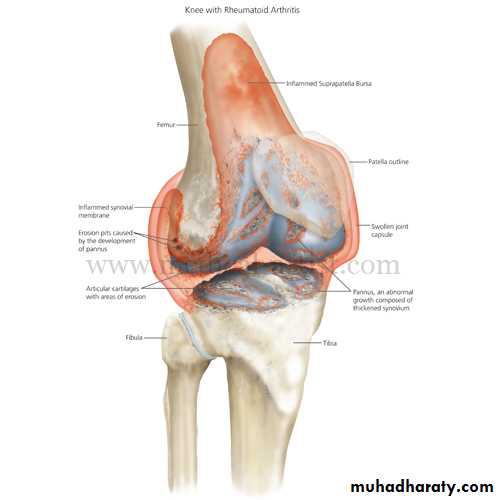

In RA, synovium become inflamed and overgrows over cartilagePannus forms = chronic hypertrophic synovial tissue

Pathologic changes begin in synovium --> infilration with leukocytes + macrophages --> pannus forms

Synovitis = feels like doughy - Spindyling of the fingers- Wrist expansion - Hand deformities (boutonniere and Swan-neck)